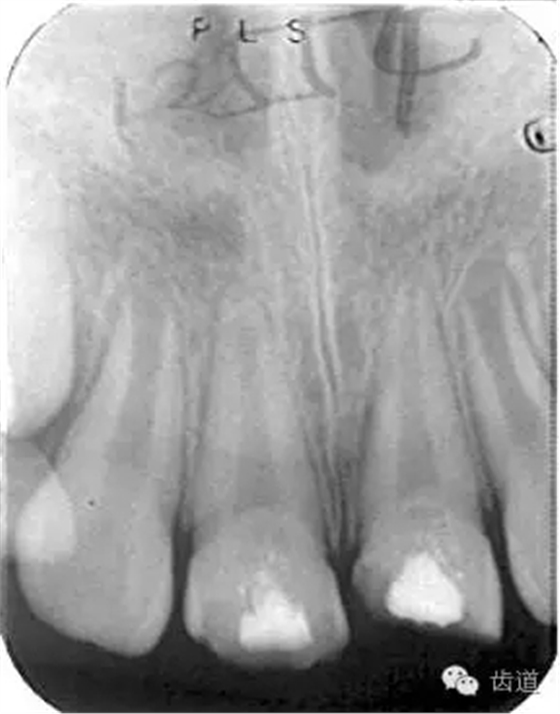

牙根發(fā)育情況-open apex

1.拍攝術(shù)前X線片;

1.術(shù)前X線片

術(shù)前

術(shù)后